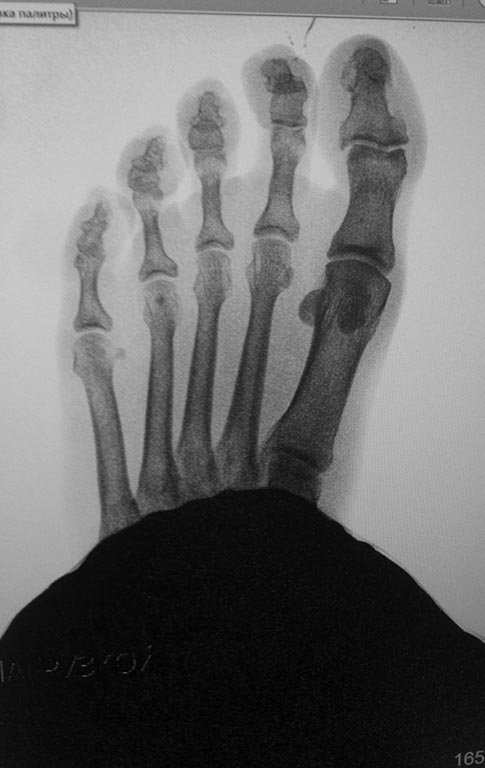

Обратилась женщина с жалобами на выраженную боль, натоптыши в области

проксимальных межфаланговых суставов V пальцев стоп.

У больной имеется деформация Тейлора ( угол М4М5 11.5 с двух сторон под

нагрузкой). В области пятого плюснефалангового сустава деформация. Боли,

гиперемии нет.

Достаточно ли в данном случае остеотомии пятой плюсневой кости с

нормализацией угла М4М5 и укорочением?